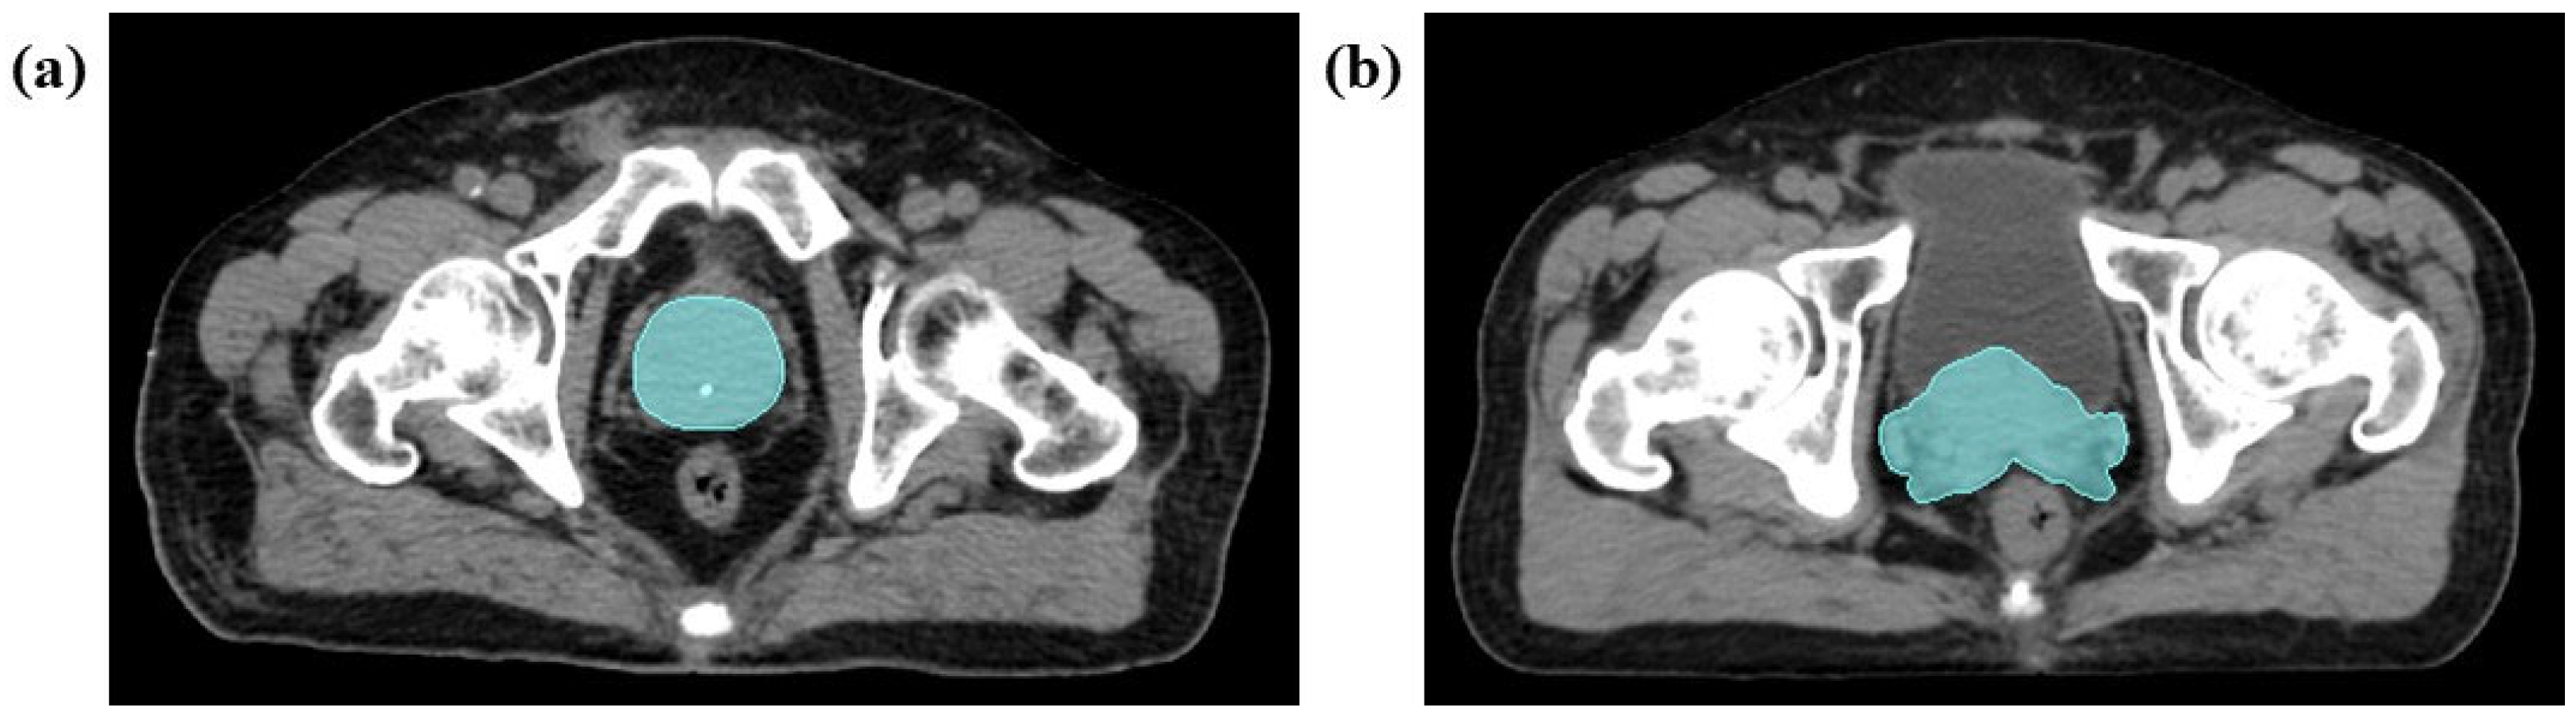

2.4.2. Medical Image Segmentation